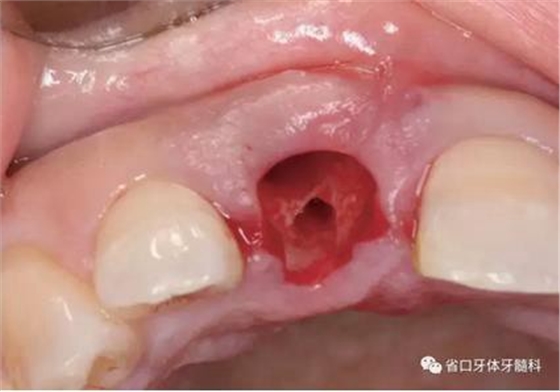

(1)微創(chuàng)拔牙及即刻種植:術(shù)前拍攝口內(nèi)照及實(shí)施牙周基礎(chǔ)治療。常 規(guī)消毒鋪巾阿替卡因局麻下微創(chuàng)拔除上頜右側(cè)中切牙,搔刮拔牙窩及根尖肉 芽組織。探測牙槽骨唇側(cè)骨壁及鄰面牙槽嵴完整,牙齦無撕裂。不翻瓣下于上頜右側(cè)中切牙缺隙近遠(yuǎn)中中點(diǎn)的腭側(cè)牙槽骨及根方定位,按照逐級預(yù)備的原則,緊貼牙槽窩腭側(cè)骨壁制備種植窩洞,植入Zimer®3.7mm×13mm TSV種植體1顆,植入扭矩>35N·cm,以O(shè)sstell測量種植體的ISQ值為68。 種植體平臺位于唇側(cè)齦緣中點(diǎn)下3mm,與唇側(cè)骨壁內(nèi)側(cè)面形成的跳躍間 隙約2mm,置入Bio-Oss®細(xì)顆粒骨粉0.25g,上愈合基臺關(guān)閉創(chuàng)口。術(shù)后 CBCT檢查顯示:種植體利用牙槽窩根方骨質(zhì)固位,緊貼牙槽窩腭側(cè)骨壁, 其唇側(cè)面與牙槽窩唇側(cè)骨壁的內(nèi)側(cè)面所形成的跳躍間隙(約2mm)可見顆 粒狀顯影物充填。牙槽窩的唇側(cè)骨壁及唇側(cè)倒凹無缺損穿孔。

圖5 微創(chuàng)拔牙

圖6 微創(chuàng)拔牙

圖7 根尖區(qū)肉芽

圖8 刮除肉芽組織

圖9 探測唇側(cè)骨壁完整

圖10 唇側(cè)骨壁完整